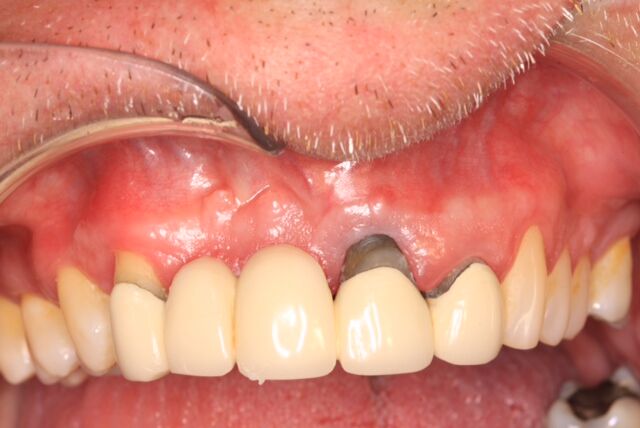

A 42-year-old man presented with a very loose bridge on Nos. 6 through 9 with periodontally compromised retainers on Nos. 6 and 9 (Figure 17 through Figure 19), and endodontically involved No. 10 with a calcified canal. Teeth Nos. 6, 9, and 10 were extracted, the sockets fully debrided, and pontic soft tissue on Nos. 7 and 8 sculpted to be symmetrical in soft tissue contour with the contralateral lateral incisor and central incisor locations. Implants were secured in position Nos. 6 through 10 (Figure 20) in excess of 45 Ncm, the bone was milled to provide unimpeded seating of temporary abutments, and temporary crowns were fabricated chairside and adjusted to be out of occlusion in centric relation and all excursions. The temporary crowns were cemented after extrusion of excess cement extraorally and the patient was prescribed antibiotics, analgesics, and instructed in postoperative care particular to immediately provisionally restored implants. At 6 months, integration was confirmed (Figure 20 through Figure 23) and after placement of scanning abutments, the implants and soft tissues were scanned. Final crowns were fabricated from the scanned images and were cemented after extrusion of excess cement extraorally (Figure 24 through Figure 26), and oral hygiene procedures were reviewed.

(19.) Initial clinical evaluation of Nos. 6 through 9 bridge and crown on No. 10.

Figure 19